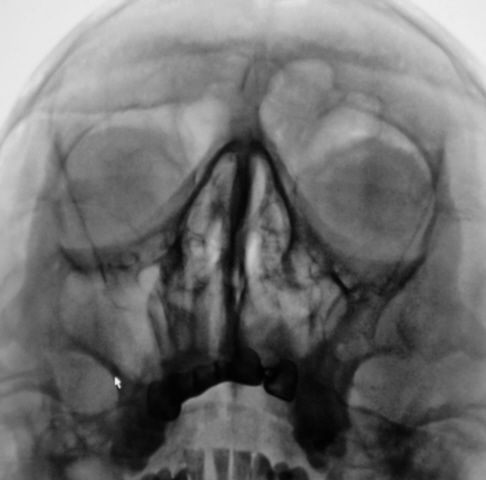

Ваше мнение коллеги по представленным снимкам и томограммам. Каждая иллюстрация представлена в двух вариантах - без обработки изображения и с "обработкой".

Четко не представляю. ) Случай интересный. Вероятно у него есть богатый анамнез с оперированной фиброзной дисплазией латеральной стенки пазухи? Какой не понять, снимки перевернуты.

Да. Перевернуты только томограммы, на которых левая сторона слева, а правая - справа. В анамнезе была операция, какая, пациент уточнить не может. В настоящее время  появились боли распирающего характера слева, чувство заложенности, направлен на исследование "без диагноза".

А перелома скуловой справа (напротив стрелки) не было?